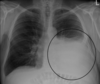

89

Joroba de Hampton = TEP

90

¿Qué es el signo de westermark?

Hiperlucencia periférica (por oligoemia)

92

Signo de Westermark = TEP